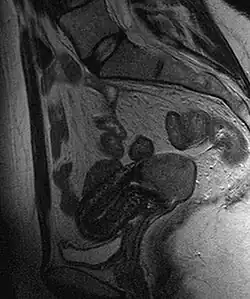

Metodou první volby v určení lokálního rozsahu onemocnění od stádia IB je magnetická rezonance (MRI). Celková senzitivita metody je 95 %).[16] Poskytuje zásadní informace pro rozhodnutí o způsobu léčby (operace či radioterapie). Informuje o velikosti nádoru a jeho případném šíření do okolí. Je nejpřesnější zobrazovací metodou pro odlišení karcinomu ohraničeného na děložní hrdlo od karcinomu infiltrujícího okolní struktury (zejména parametria, přesnost je více než 90%).[17] Klinické vyšetření je nejpřesnější v odhadu infiltrace do parametrií, močového měchýře a konečníku, naopak kolposkopie je přesnější v hodnocení infiltrace pochvy.

Většina pacientek má v době vyšetření již histologicky stanovenou diagnózu a MR vyšetření je tedy určené primárně na posouzení rozsahu, ne na detekci onemocnění.

Magnetická rezonance se také považuje za nejlepší zobrazovací metodu pro plánování radiochemoterapie a pro sledování lokální reakce na léčbu. Po šesti měsících od operace je MR schopná zodpovědně odlišit pooperační jizvovitou tkáň od lokální recidivy onemocnění.

Magnetická rezonance nedokáže vzájemně odlišit jednotlivé histologické typy karcinomu děložního hrdla. Problematické je zobrazení zejména při malých adenokarcinomech, které rostou difuzně a jejichž signál je podobný signálu okolní stromatů.

Základem pro zobrazení karcinomu děložního hrdla je T2 vážení (přístroj s hodnotou magnetického pole 1-3T, matrix 512, hloubka řezů 4–5 mm, fázové rozlišení nejméně 75 %), přičemž se vyšetřuje minimálně ve dvou rovinách (nejprve v dlouhé ose hrdla – sagitální rovina, poté kolmo na dlouhou osu – tranzverzální či šikmá tranzverzální rovina). Součástí standardního protokolu na určení stádia onemocnění by mělo být i vyšetření paraaortálních lymfatických uzlin (tedy kromě pánve i vyšetření dolního břicha). Ke standardním sekvencím dále patří tranzverzální sekvence v T1 vážení (6mm, matrix 512, fázové rozlišení nejméně 60 %), určená na posouzení bočních stěn pánve a lymfatických uzlin. Podávání nitrožilní kontrastní látky není při primárním stagingu potřebné, v individuálních případech může pomoci při identifikaci infiltrace rakoviny do stěny močového měchýře či konečníku.[18] Podání kontrastní látky s následným rychlým dynamickým vyšetřením (ultrarychle T1 GRE sekvence) je naopak potřebné při rozlišení recidivy rakoviny od pooperačních a poradiačních změn.

Nejdůležitějším prognostickým faktorem je velikost nádoru a přítomnost metastáz v lymfatických uzlinách. Gynekologické vyšetření má sklon skutečnou velikost podcenit. MRI dokáže identifikovat nádory od velikosti 1 cm a objektivně stanovit jejich velikost (objem); v případě vnějšího edému naopak skutečnou velikost spíše přeceňuje.